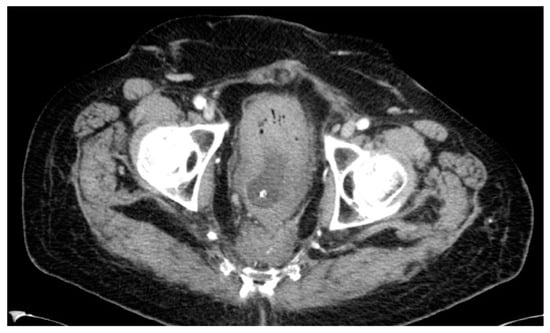

| 50 years | Female | ypT3ypN2a | 6 months | Lateral/nodal |

| 76 years | Male | ypT2ypN1 | 135 months | Lateral/nodal |